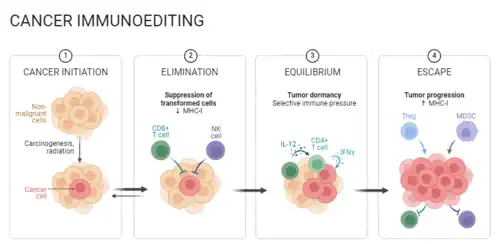

Atualmente, a imunoedição e expressão de HLA são passos importantes na evolução da evasão imunológica e resistência a medicamentos do câncer. A imunoedição descreve um processo de três etapas no qual a seleção pelo sistema imunológico conduz a evolução do tumor em direção à evasão imunológica. Por meio do reconhecimento das células cancerígenas e montagem de uma resposta contra elas, fase de eliminação, os clones imuno resistentes, se surgissem antes da erradicação do tumor, através de mecanismos como instabilidade genômica ou plasticidade epigenética, poderiam ser suficientes para conduzir um tumor a uma fase de equilíbrio. Esta, a qual a morte imunomediada é proporcional à proliferação de células tumorais, tendo nenhum crescimento líquido do tumor ocorrendo. A morte de clones pode, então, selecionar clones imunes evasivos, levando ao escape e ao crescimento de um tumor imune evasivo.[38]

A perda de expressão de HLA I resulta na incapacidade de infiltração de linfócitos. Com o desenvolvimento da seleção imunológica, o número de células negativas para HLA I no tumor aumentou gradualmente, permitindo que as células formem nódulos cancerígenos através do microambiente imunossupressor, impedindo a entrada de linfócitos. Assim, alguns tumores podem ser insensíveis ao tratamento porque têm expressão ou superexpressão de HLA, o que os ajuda a completar o escape imunológico [39]